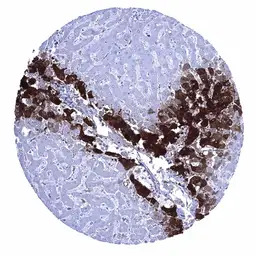

IHC-P analysis of human liver tissue section using GTX04471 Glutamine synthetase antibody [MSVA-750M] HistoMAX.

Glutamine Synthetase staining is strong in centrilobular hepatocytes weak to moderate in Kupffer cells but absent in periportal hepatocytes.